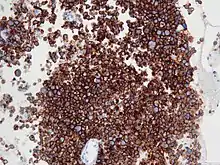

| Micrograph of an anaplastic large-cell lymphoma. H&E stain. | |